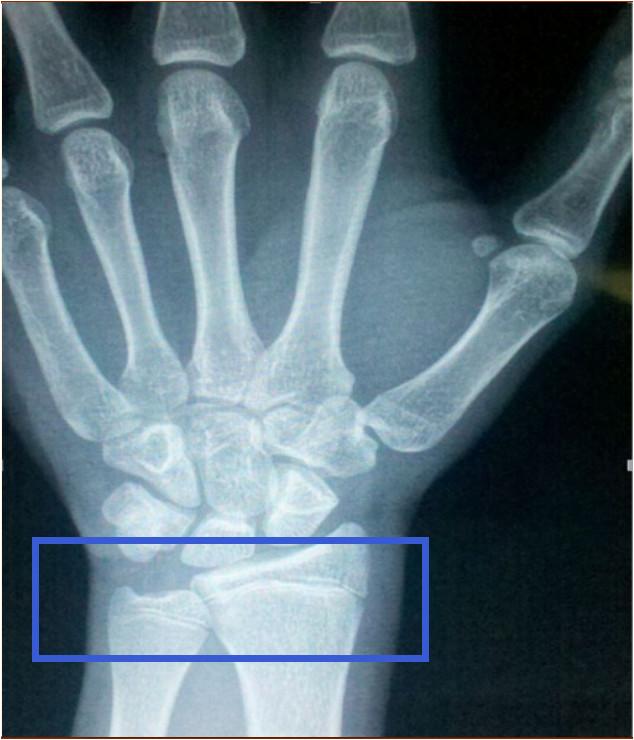

如何确诊指骨骨骺早闭?